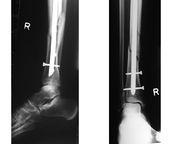

- Osteosynthesa znamená operační řešení, při kterém je kost zpevněna nejčastěji kovovým materiálem, kterým je nějaký druh nerezové oceli nebo titanu, který se po čase buď vyjme, nebo někdy i ponechá. Existuje řada metod, od jednoduchých cerkláží ocelovými dráty, přes šrouby doplněné dlahami až po nejrůznější systémy hřebování s předvrtáváním nebo bez něj (hřeb znamená navlečení nejčastěji dlouhé a duté kosti na pevný a dlouhý ocelový profil, který je na konci zafixován šrouby. Po čase se šrouby na jednom zpravidla distálním (vzdáleném) konci vyjmou, čemuž se říká dynamizace).